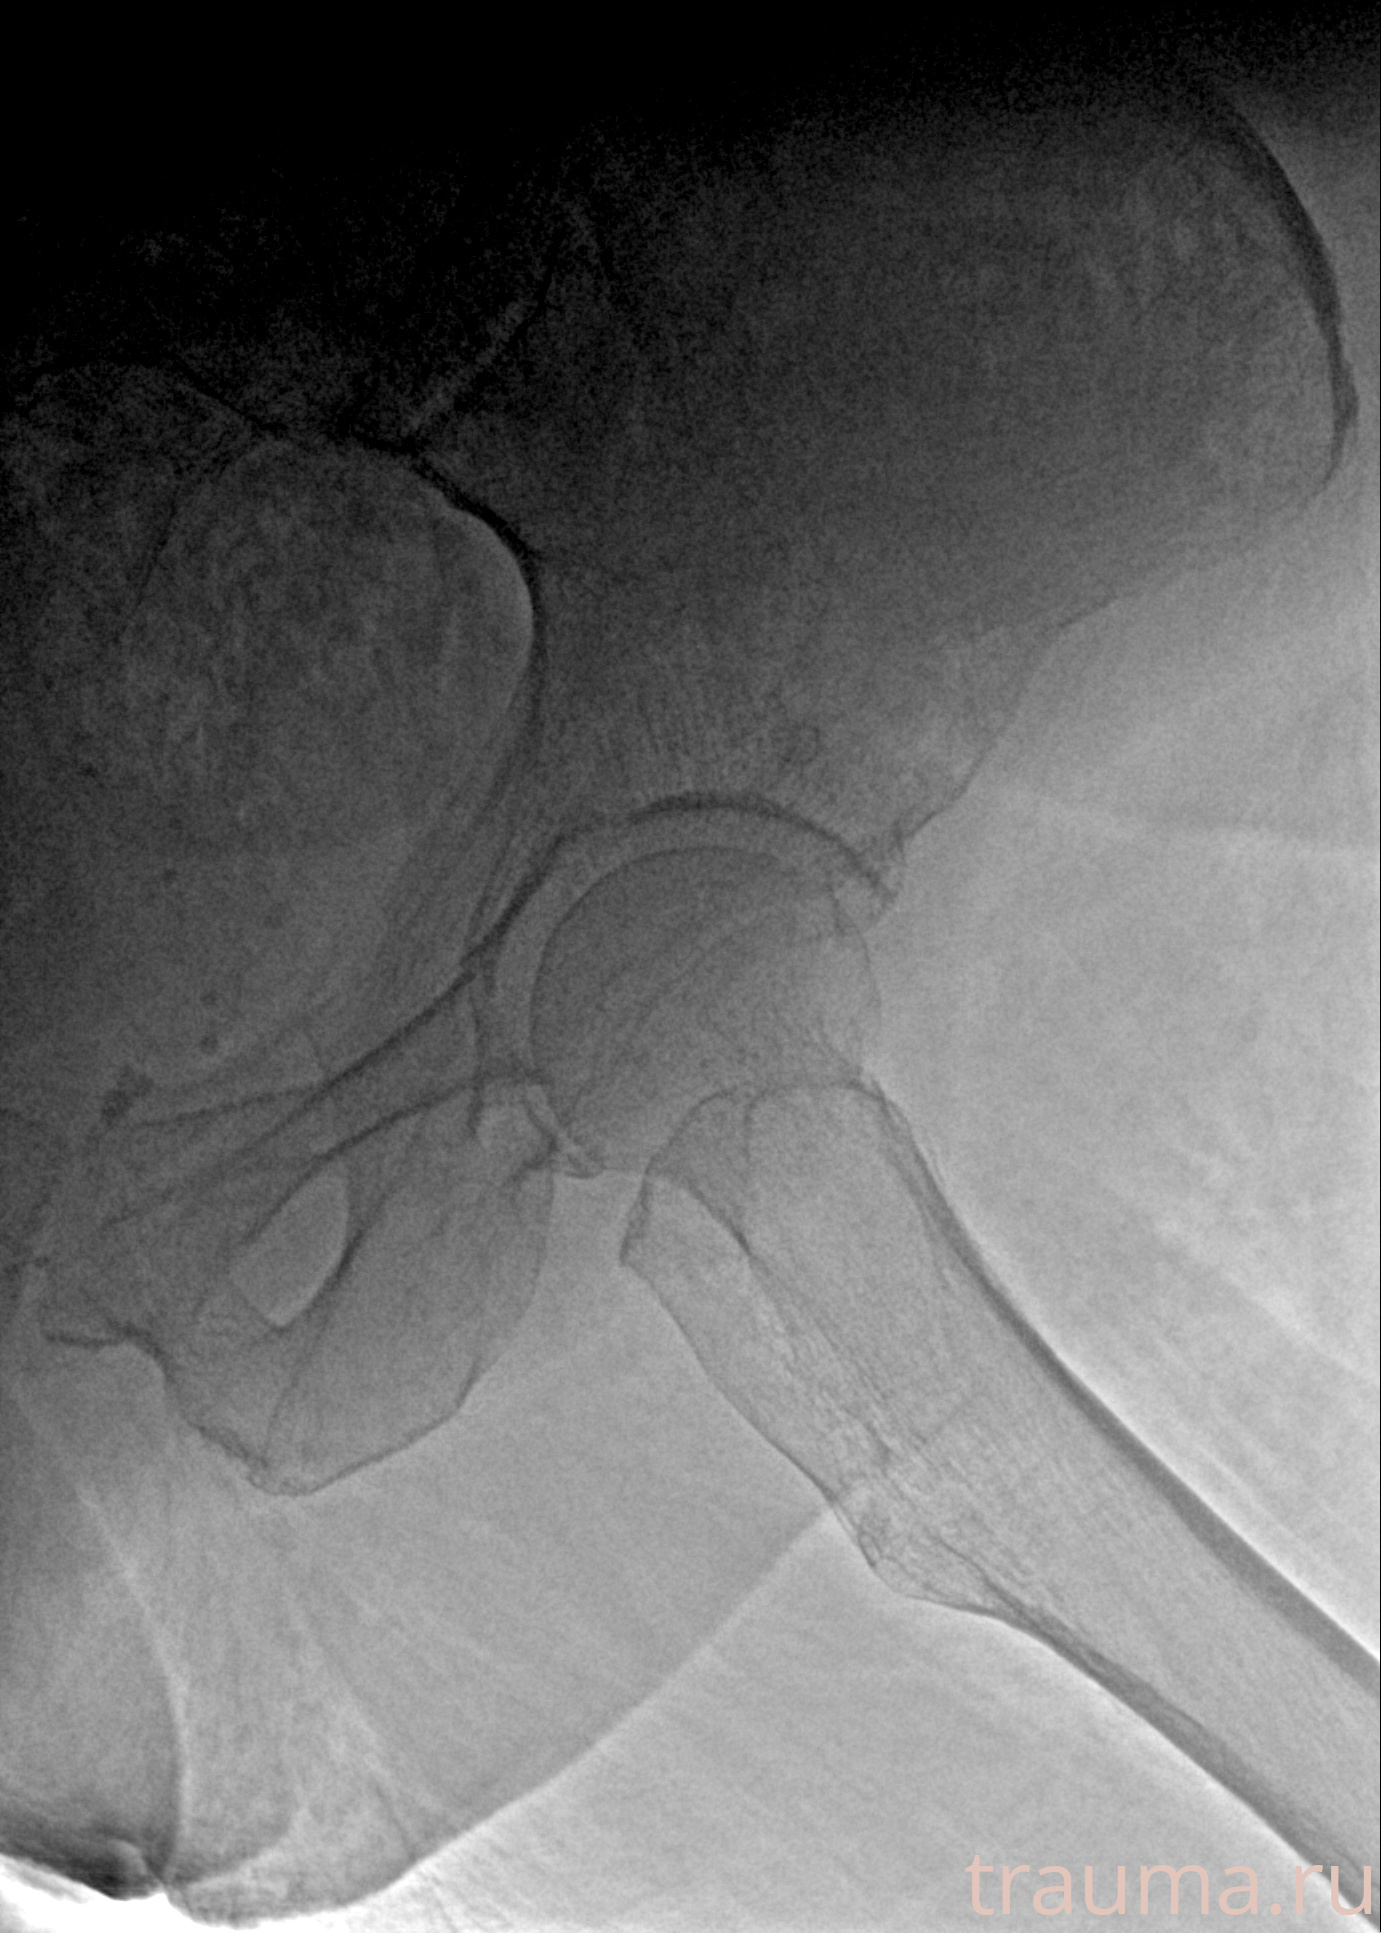

Рентгенограммы

Рентген на дому: по вашему адресу приезжает врач-рентгенолог, травматолог-ортопед с мобильным рентгеновским аппаратом, проводит диагностику травмы или заболевания, делает необходимые рентгенограммы, дает рекомендации по дальнейшему лечению. Получить качественные снимки в домашних условиях возможно благодаря уникальной методике, разработанной МосРентген Центром для института  Склифосовского